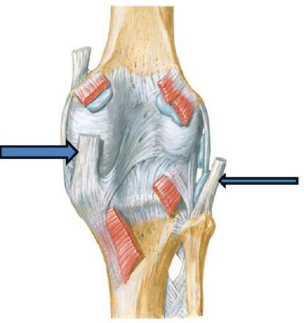

Figura para responder à questão.

Figura para responder à questão.